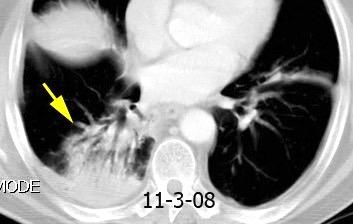

VIH+. 1 mes antes derrame pleural en el curso de una

infección

Huggins